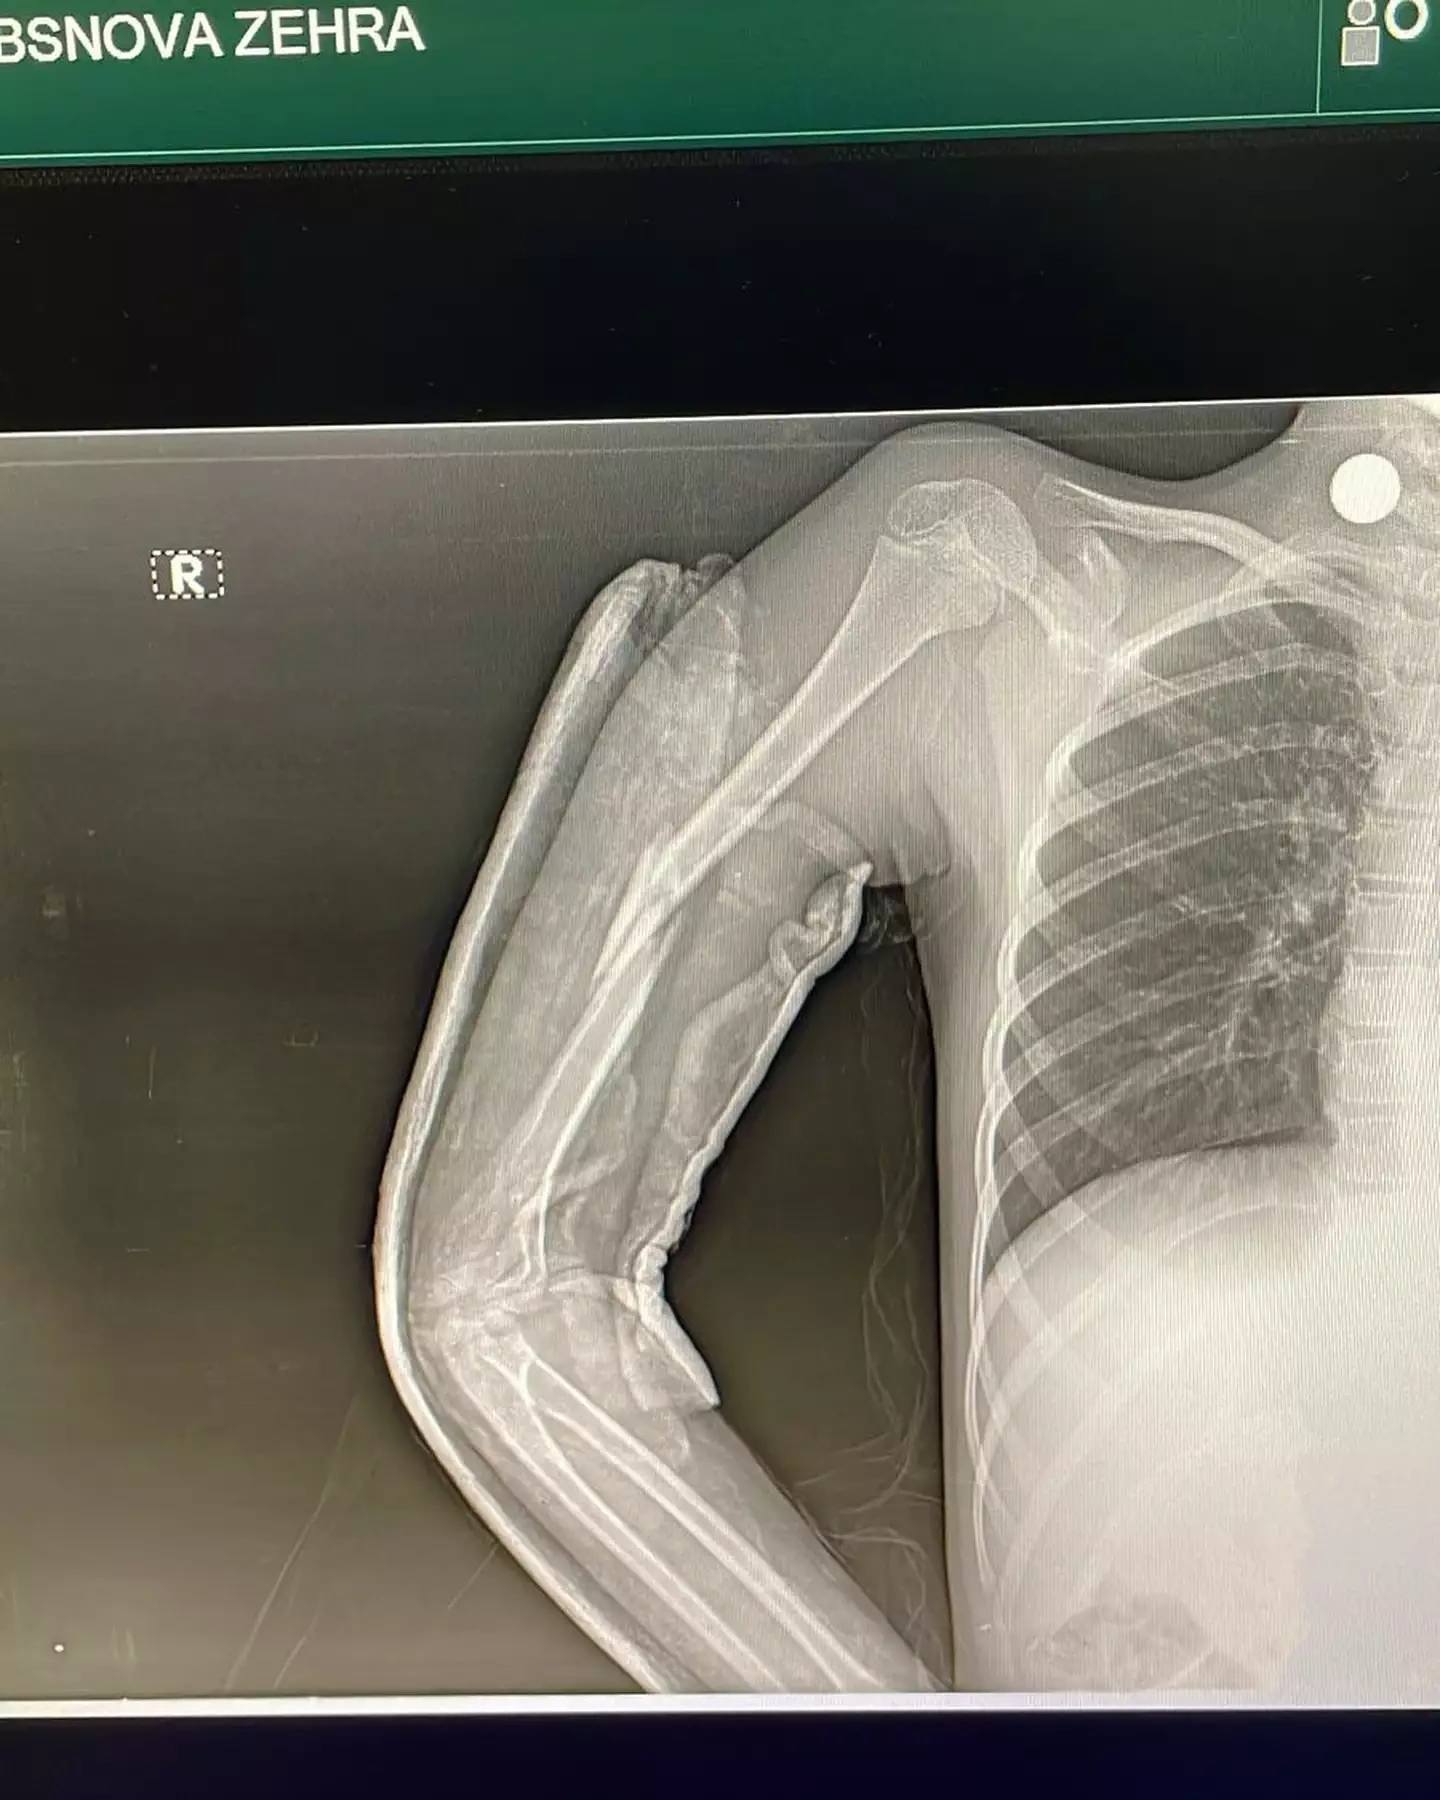

Hadisədən yalnız iki azyaşlı xilas ola bilib. Nərmin bildirib ki, onların da səhhətlərində ciddi problemlər yaranıb və maddi dəstəyə ehtiyacları var.